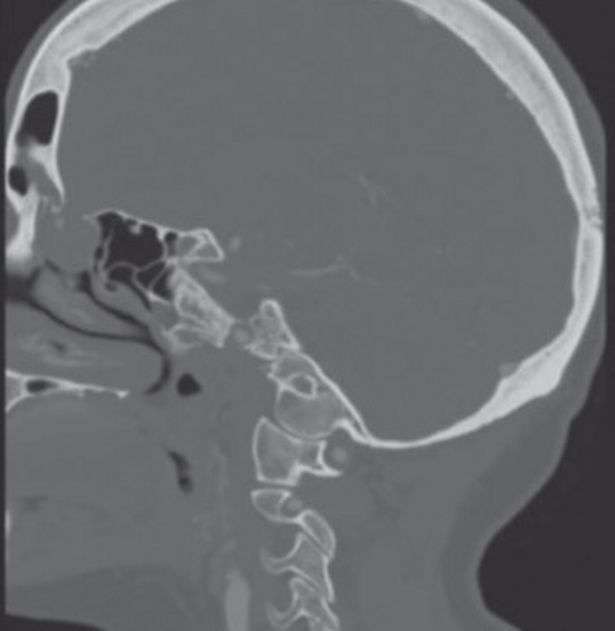

CT Scan mengidentifikasi sebuah struktur seperti kantung berukuran 1,8 cm yang menonjol ke dalam rongga hidung di antara kerusakan pada tulang.

Kantung itu merupakan ensefalokel, sebuah kondisi yang biasanya diidentifikasi pada bayi di mana tulang tengkorak tidak menyatu sepenuhnya, menciptakan celah di mana cairan serebral dan jaringan otak dapat berkumpul di benjolan yang menonjol.

JAMA Otolaryngology/University of Iowa Hospitals and Clinics

Dokter membandingkan hasil penelitian tersebut dengan CT Scan yang dilakukan pada pasien 3 tahun yang lalu.

Mereka menemukan encephalocele pernah ada, tetapi salah didiagnosis sebagai penyakit sinus paranasal atau peradangan pada sinus.